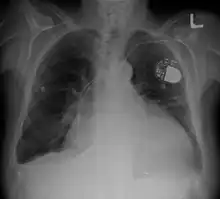

| Cardiomegaly on chest X-ray with a pacemaker | |

- Chest X-ray: X-ray images help to visualize the condition of the lungs and heart. If the heart is enlarged on an X-ray, other tests will usually be needed to find the cause. A useful measurement on X-ray is the cardio-thoracic ratio, which is the transverse diameter of the heart, compared with that of the thoracic cage.[24] These diameters are taken from PA chest x-rays using the widest point of the chest and measuring as far as the lung pleura, rather than lateral skin margins. If the ratio is greater than 50%, pathology is suspected.[25] The measurement was first proposed in 1919 to screen military recruits. A newer approach to using these x-rays for evaluating heart health takes the ratio of heart area to chest area and has been called the two-dimensional cardiothoracic ratio.[26]